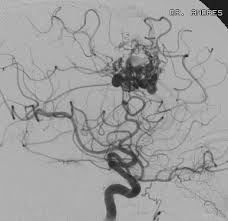

Malformaciones cerebrales arteriovenosas

Las malformaciones arteriovenosas son anomalías vasculares congénitas que se originan a partir de un desarrollo inadecuado localizado de una parte del plexo vascular primitivo. Estas malformaciones se caracterizan por la…